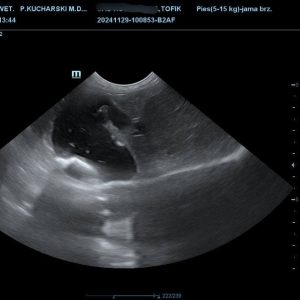

14.12.2024 Szanowni Państwo, przepraszam za wiadomość w sobotę, ale sytuacja jest krytyczna. Tofik, piesek, który dzięki Wam w czwartek przeszedł operację usunięcia kamieni w pęcherzyku żółciowym, wczoraj wieczorem zasłabł i trafił w ciężkim stanie do kliniki całodobowej, gdzie lekarze walczą o jego życie.

W kwietniu tego roku Tofik zachorował, czym prędzej udała się z nim do weterynarza. Okazało się, że jej futrzasty przyjaciel ma kamienie w pęcherzyku żółciowym. Weterynarz początkowo ocenił, że wystarczy zastosować leczenie zachowawcze, jednak okazało się, że terapia nie przyniosła oczekiwanych rezultatów, a kamień, tylko się powiększył.

W tej chwili istnieje wysokie ryzyko, że może on zatkać drogi żółciowe, a gdy pęcherzyk pęknie, dojdzie wówczas do zapalenia otrzewnej, co jest bezpośrednim stanem zagrożenia życia! A wtedy będzie już za późno na ratunek. Jedną opcją, aby ocalić Tofika przed najgorszym, jest bardzo droga operacja, na którą seniorki po prostu nie stać.